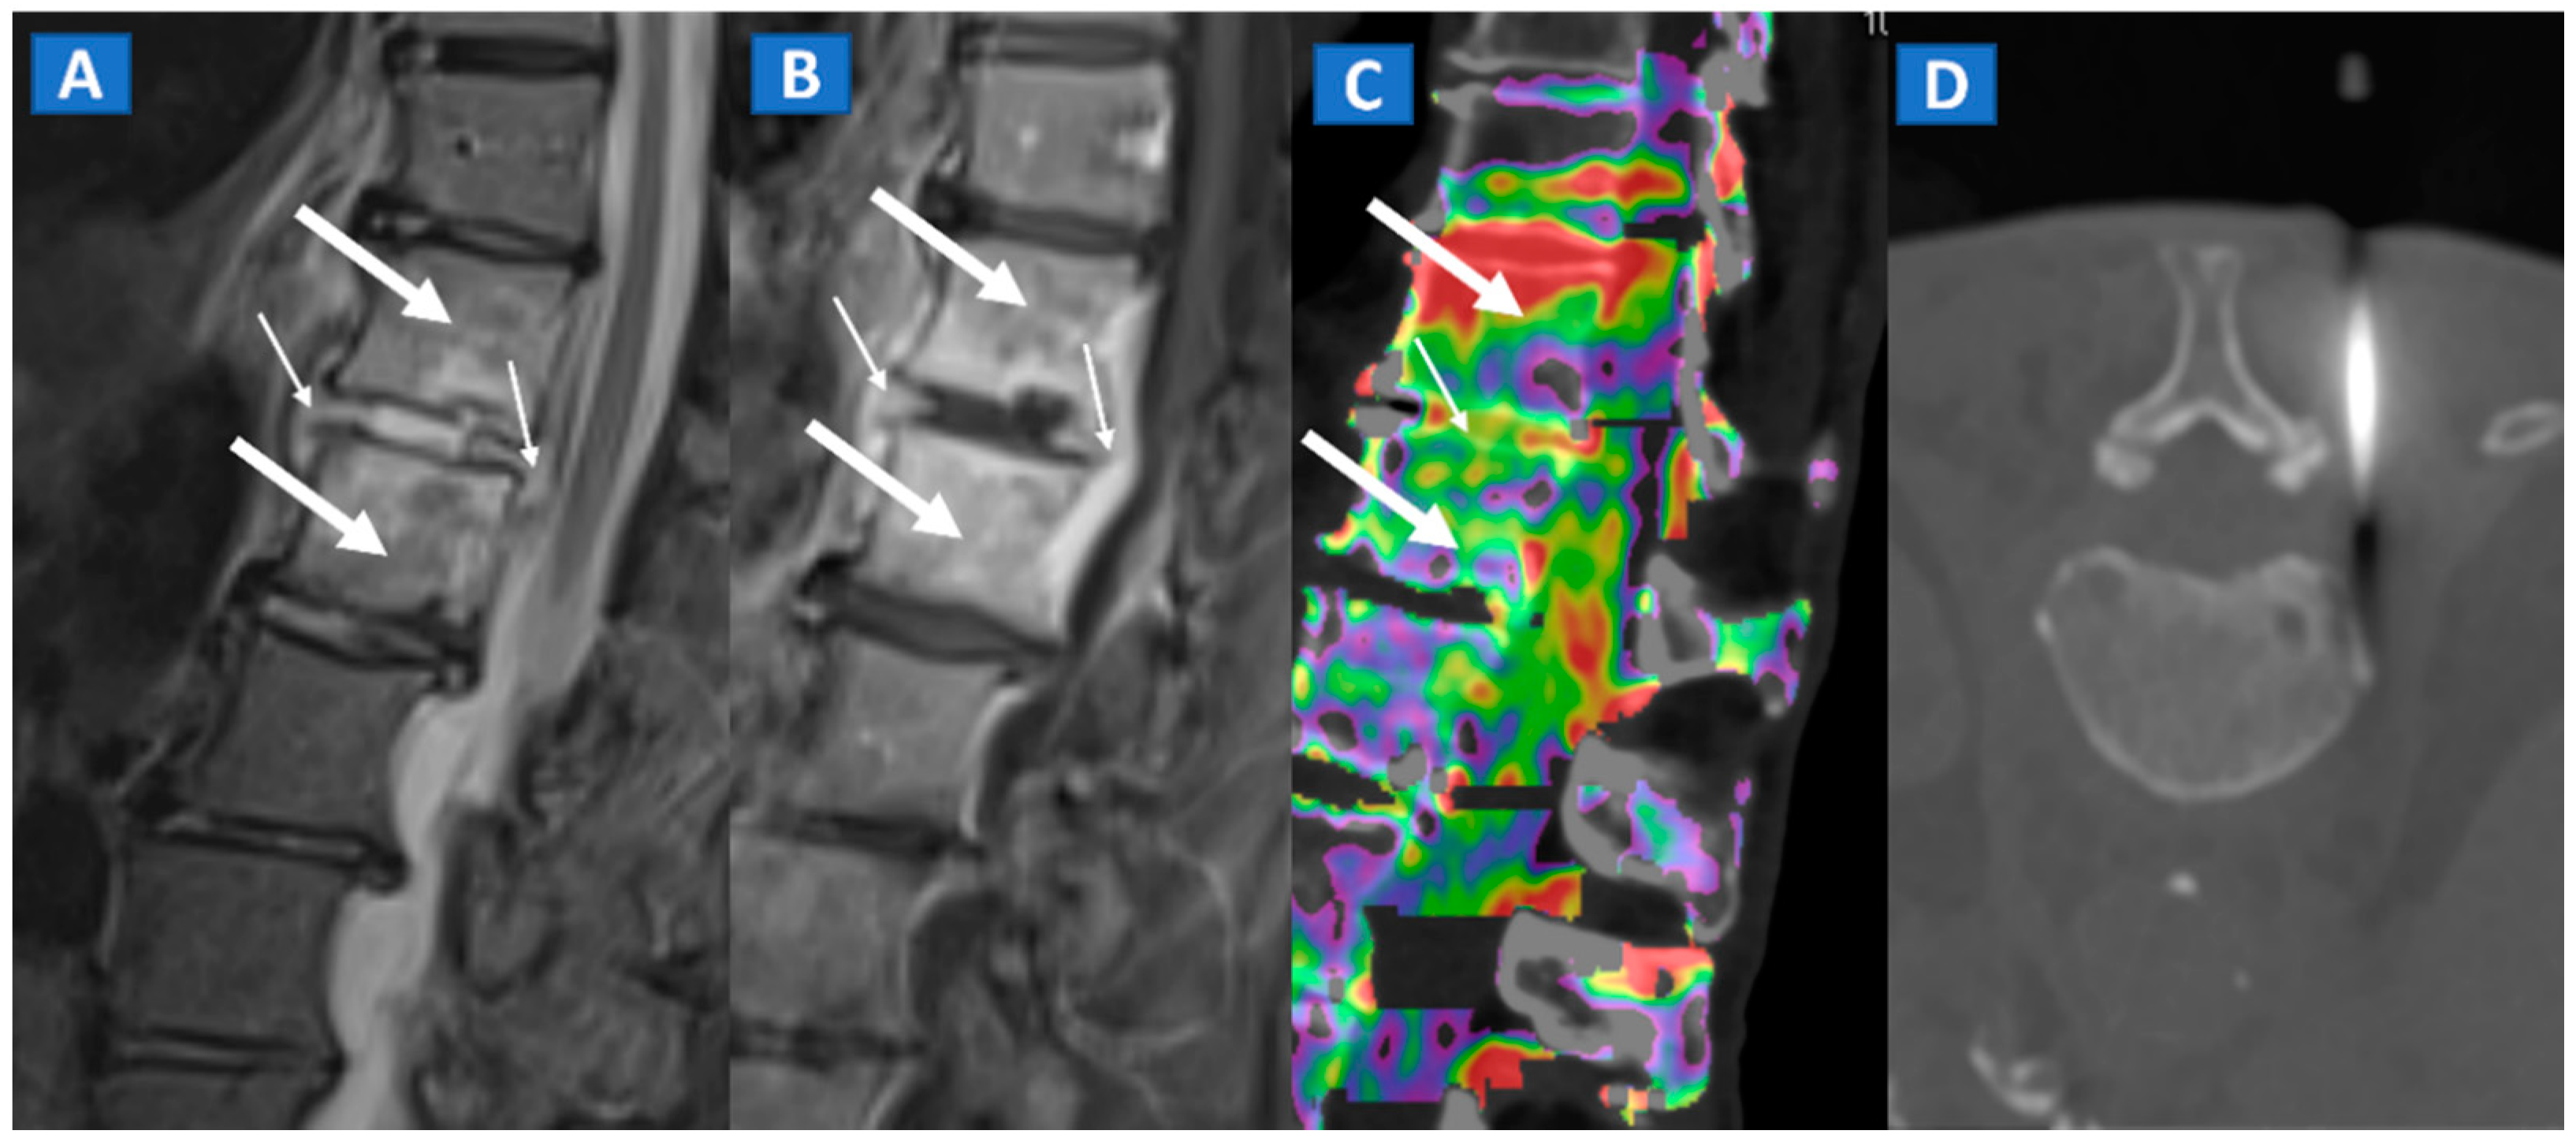

11. Infectious Diseases

Bone inflammation due to infective diseases involving skeletal system, is often characterized by the presence of BME at imaging. In case of spondylodiscitis, DECT can depict the presence of vertebral bodies and intervertebral disc oedema (Figure 10), which can rule out endplate erosion or vertebral collapse. Furthermore, CT can be used to guide sampling during paraspinal fluid collections. In case of osteomyelitis, DECT could be employed to depict BME, but also to clearly depict erosive changes, lytic lesions, as well as soft tissue involvement.

Figure 10.

A 57-year-old male diagnosed with spondylodiscitis, and presenting with worsening low back pain. On the sagittal STIR MRI image (A), BME of the L1 and L2 vertebral bodies is apparent (thick arrows). The intervertebral disc appears hyperintense, with thickening of the anterior and posterior longitudinal ligaments (thin arrows). On the corresponding sagittal T1-weighted image (B) after intravenous administration of gadolinium, contrast enhancement is depicted, involving vertebral bodies (thick arrows) and thickened anterior and posterior longitudinal ligaments (thin arrows). On the DECT sagittal 1 mm reconstructed image (C), there is BME involving vertebral bodies (thick arrows) and the disc (thin arrow). Under CT guidance (D), sampling on para-spinal fluid collection was performed to confirm the diagnosis of spondylodiscitis and to isolate the pathogen involved.